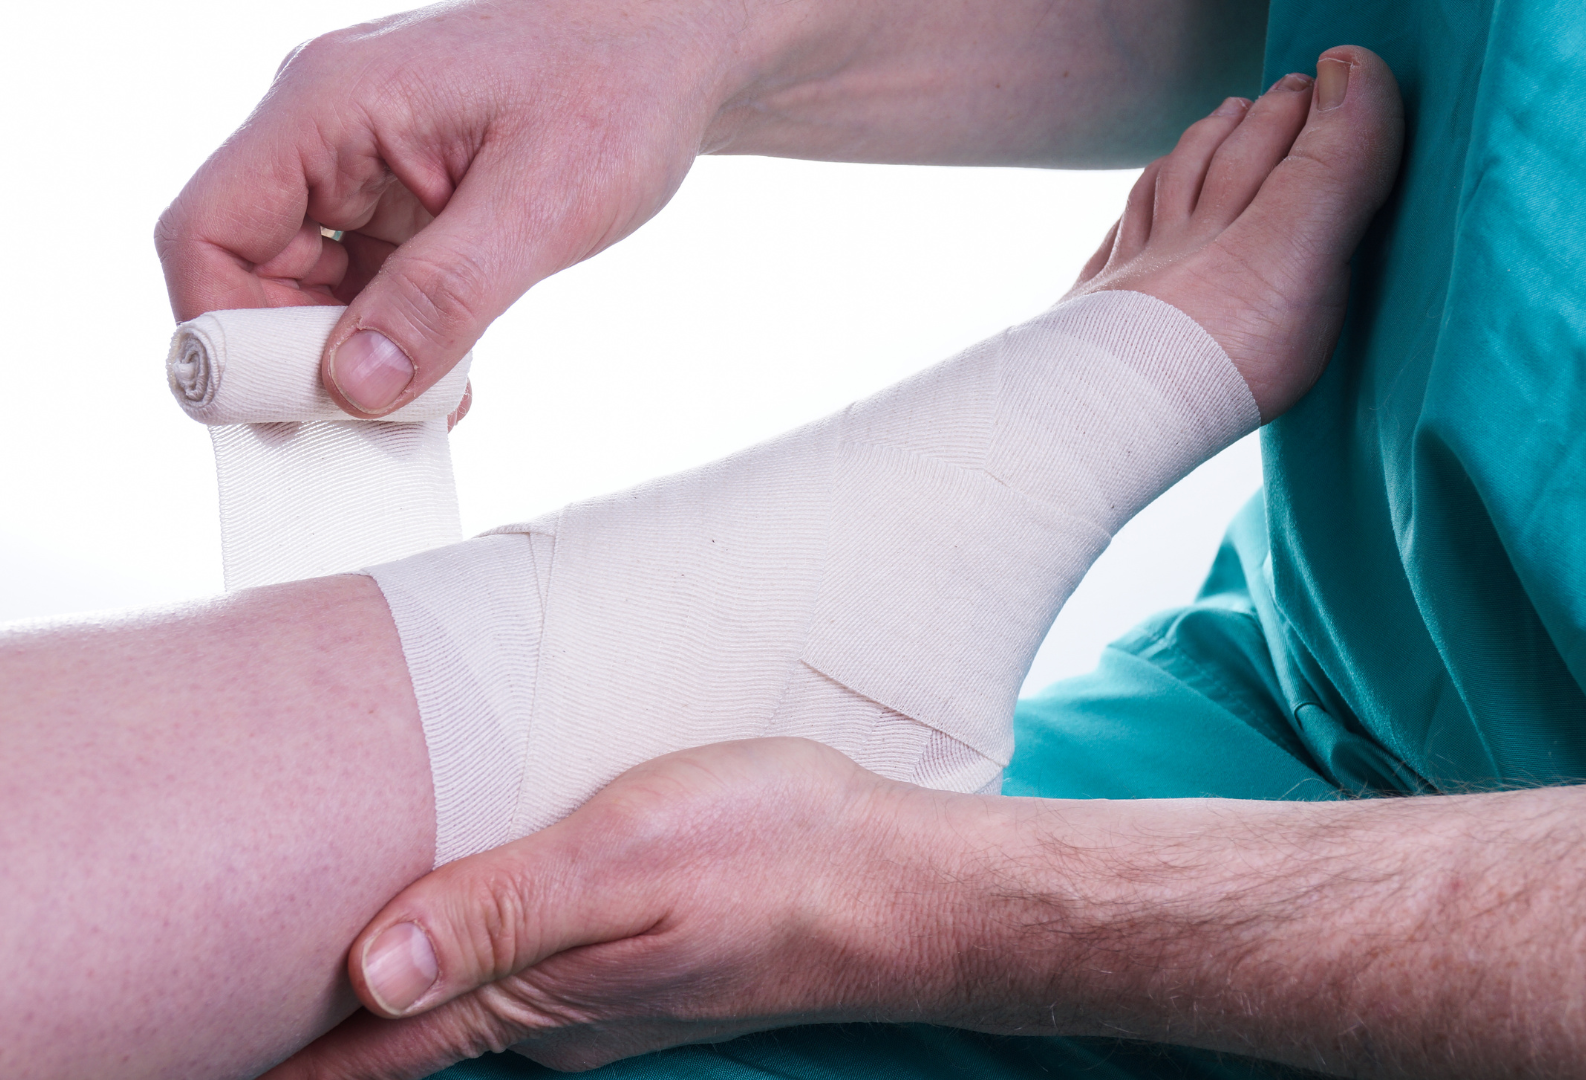

2. 早く治るための「適切な固定」

正しい診断がついたら、次に行うのが「適切な固定」です。

現在は、骨折を合併していない靭帯損傷(I度〜III度)の場合、サポーターや装具を用いて、

足首が内側に捻れないように保護しつつ、ある程度の動き(特に前後の動き)は許容する「機能的固定」が推奨されています。

腫れや痛みが非常に強い場合や、前述のような骨折を合併している場合は、やはり1ヶ月、場合によってはそれ以上のギプス固定が必要となります。